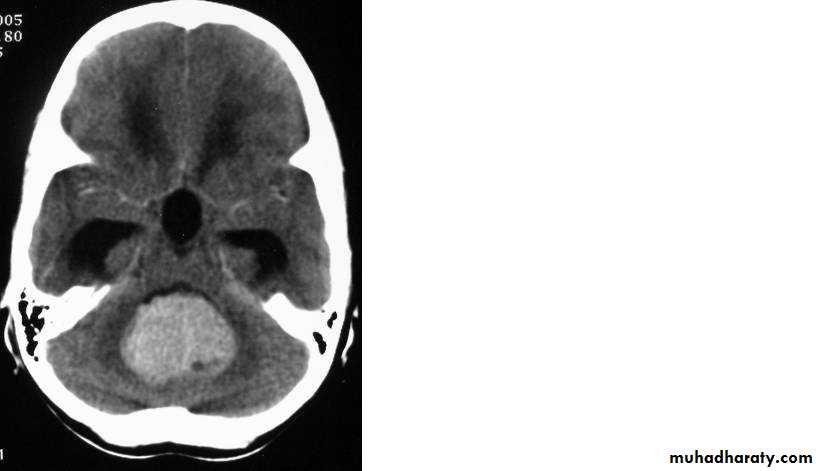

AstrocytomaPre contrast CT

AstrocytomaPost contrast CT

Astrocytoma Pre contrast MRI

Astrocytoma Post contrast MRI